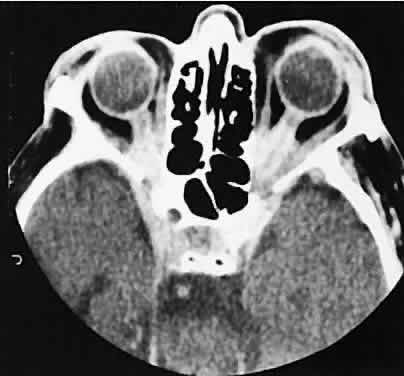

| The orbital manifestations of a vascular process are dependent on whether

the lesion is on the venous or the arterial circulation. Patients with

venous lesions (varix) characteristically report a history of intermittent

proptosis with either a Valsalva's-type maneuver or having

the head in a dependent position. Suspicion of a venous varix should

alert the radiologist to perform the scan before and after a Valsalva's

maneuver.9,10 Color flow doppler imaging showing reversal of flow during a Valsalva

maneuver also is a helpful finding. Phleboliths may or may not be present. Another

clue to the diagnosis of a varix is the location, many times

in the posterior, inferior lateral orbit, seemingly coming out of

the inferior orbital fissure near the apex. Lesions that appear to change

size or shape from the axial view to the coronal view also have turned

out to represent a varix based on our experience (Fig. 2). Arterial lesions may either have high or low flow. The high-flow lesions are carotid cavernous sinus fistulas and result from a direct communication between the carotid artery and the cavernous sinus. These arise spontaneously or as a result of trauma. The orbit is involved as an innocent bystander, because all signs and symptoms of orbital involvement follow from the retrograde transmission of increased venous pressure from the cavernous sinus. EOMs generally are enlarged, as is the SOV. The ipsilateral cavernous sinus also is enlarged. Intercommunication between the cavernous sinuses also may account for the occasional bilateral findings. Low-flow lesions result from increased blood flow through the cavernous sinus, but the intracavernous carotid artery itself is intact (Fig. 3). These typically are dural-cavernous sinus fistulas. A high index of suspicion may be required to diagnose these, but a fairly stereotyped presentation is a unilateral red-eyed glaucoma with proptosis. Abduction weakness also may be present. Enlargement of one or more EOMs along with an enlarged SOV are noted with CT scanning. A small lesion may escape detection with CT scanning and require high-resolution MRI or even selective internal and external carotid angiography for diagnosis if a high degree of clinical suspicion exists. In a patient with a known dural fistula, a sudden and dramatic deterioration in the clinical picture may be seen with a thrombosis of the SOV.11 The radiographic picture, at least regarding the CT appearance, probably will not change. MRI can nicely show the thrombosis in the SOV.